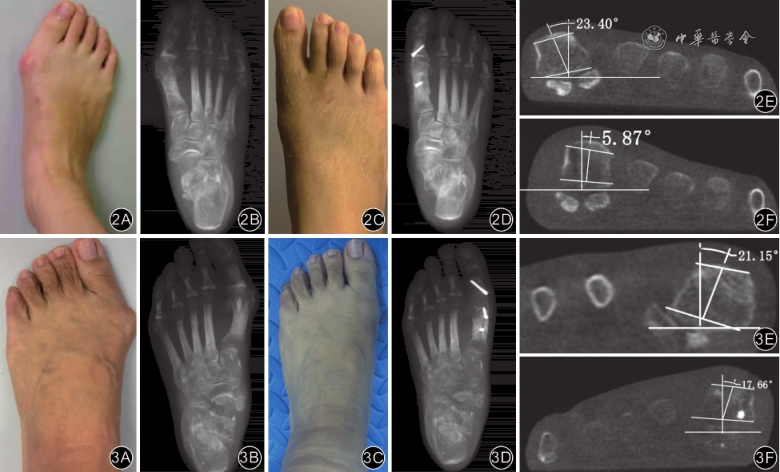

2组间患者的术前影像学指标HVA、IMA、DMAA、TSCG、α角比较差异均无统计学意义(P值均>0.05)。末次随访时,除传统Scarf组DMAA与术前比较差异无统计学意义外(Z=-0.54,P=0.586),2组患者的其他各项指标均较术前改善,差异均有统计学意义(P值均<0.05)。末次随访时,2组间比较HVA、HVA纠正量及IMA差异均无统计学意义(P值均>0.05);但改良单钉Scarf组α角、DMAA及其对应的纠正量,以及IMA纠正量、TSCG均优于传统Scarf组,差异均有统计学意义(P值均<0.05)。见表2、3。

| 术前[°,M(Q1,Q3)] | 22.9(21.0,25.6) | 22.3(20.3,26.7) | Z=-0.41 | 0.686 |

| 末次随访[°,M(Q1,Q3)] | 10.2(6.4,15.2)a | 15.2(10.5,18.4) a | Z=-2.33 | 0.020 |

| 纠正量[°,M(Q1,Q3)] | 13.2(8.1,17.0) | 8.9(3.7,11.7) | Z=-2.51 | 0.012 |

Scarf截骨术具有矫形能力强、内在稳定性大、截骨面接触广、骨质愈合快、不干扰第1跖骨干的血运,以及可以有多种调整截骨适应不同患者等优点[14, 15],因此,在拇外翻的治疗中得到很好地应用,并且疗效确切。由于截骨术的特点是截骨块远端为面对面接触,因此,无法人为增加对第1跖骨旋转的纠正。而第1跖骨旋转在拇外翻畸形中扮演了很重要的角色,也是近年来研究比较多的课题[16, 17, 18]。α角是目前文献报道中评价第1跖骨冠状位旋转较可靠的指标[10,19, 20]。本研究通过负重CT分析发现,传统Scarf截骨术纠正第1跖骨旋转平均约7°,这与Peng等[21]报道的结果基本一致,虽然这个纠正量可观,但对于旋前较大的拇外翻患者显然不适用;改良单钉Scarf组对第1跖骨旋转纠正了中位度数约13°,明显优于传统Scarf组,这主要得益于卡槽的制作,使得两截骨块远端的接触由传统Scarf面对面的四边形,变成了远端纵向面对近端水平面的三维复杂结构,骨面的接触在轴向上进行了90°的扭转,因此具有调整轴向旋转的能力。我们通过克氏针操作杆手法纠正后透视检查,再于近端增加1枚螺钉控制已经纠正的旋转量,可完全纠正旋转,同时保持了纠正后的骨结构位置。经过平均10.6个月的随访,结果显示这种纠正方式不会因骨愈合丢失,也不会因跖楔关节没有融合而复发。这种纠正方式并不像Lapidus截骨术那样从跖楔关节平面进行纠正,而是基于跖骨干本身。Ota等[22]的观点认为,第1跖骨的旋转是由于跖骨干本身的扭转,而非起源于跖楔关节。Lalevée等[23]通过负重CT的研究也发现,跖骨干扭转在第1跖骨旋转中起重要作用。

传统Scarf截骨术对DMAA的纠正能力也有限。Xiong等[24]对47例行传统Scarf的患者进行了24个月的随访,发现DMAA从术前的9.38°±2.53°降低到术后的6.32°±0.77°,DMAA仅仅改变了3°。本研究中传统Scarf组对DMAA的纠正能力与先前文献报道的差异不大。主要有以下几种原因:(1)截骨过程中没有注意第1跖骨旋转的纠正,而Lalevee等[25]发现使用负重CT测量纠正第1跖骨冠状位旋转后的DMAA较前减小,也就是说纠正跖骨旋前在一定程度上可以纠正DMAA,而传统Scarf纠正旋转能力有限,所以对DMAA的纠正也会相应不足。(2)传统Scarf截骨后在移位过程中近端和远端应当同时向外推移,如果单纯推移远端甚至会导致DMAA的增大。(3)DMAA测量时常出现假象,在纠正IMA后DMAA角会相应减小。传统Scarf截骨术的截骨特点限制了其应用范围,而改良术式增加了对DMAA的纠正能力:首先,其对于第1跖骨旋转的纠正可以在一定限度上减小DMAA[25];其次,改良单钉Scarf截骨术截骨后有很大自由度,如果DMAA纠正不满意,近端可以向外侧移位更多,从而在水平面上纠正DMAA。本研究结果可以看出,改良单钉Scarf组对于DMAA的纠正明显优于传统Scarf组。

籽骨复位不良是拇外翻矫形手术失败的重要因素,籽骨复位满意可以达到更好的术后效果[26]。籽骨的脱位是旋前脱位,这一改变常常伴有跖骨旋前的存在,纠正第1跖骨旋前即可达到籽骨复位[10]。在本研究中,末次随访时2组TSCG差异有统计学意义,改良单钉Scarf组的TSCG 0级的占比最大,而传统Scarf组1级的占比最大,可见改良单钉Scarf组的籽骨复位更完全。